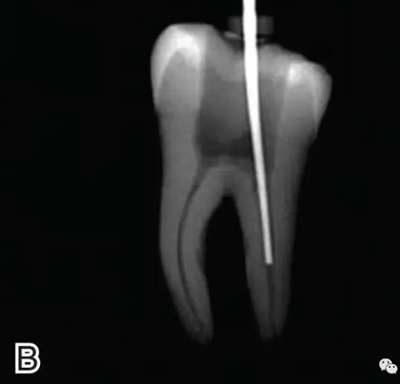

要求工作尖能自由到達(dá)距根尖4~5 mm(有學(xué)者提出3~4 mm)的位置并能輕微接觸根管壁,用橡皮片做好標(biāo)記(圖1)。

圖1 選擇攜熱器工作尖,A.試攜熱器尖 B.工作尖在根內(nèi)的位置